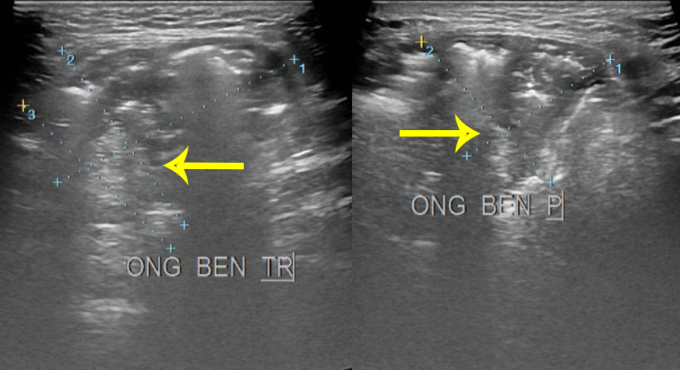

Ban đầu ông tự điều trị bằng phương pháp băng ép, đẩy khối phồng lên nhưng không hiệu quả. Khi vùng bẹn tổn thương, ông đến Bệnh viện Đa khoa Tâm Anh Hà Nội kiểm tra. Hình ảnh siêu âm cho thấy bệnh nhân bị thoát vị bẹn hai bên, kích thước mỗi khối khoảng 3×4 cm, chưa có dấu hiệu nghẹt.

Các khối thoát vị hai bên bẹn của ông Ờ trên phim siêu âm. Ảnh: Bệnh viện Đa khoa Tâm Anh